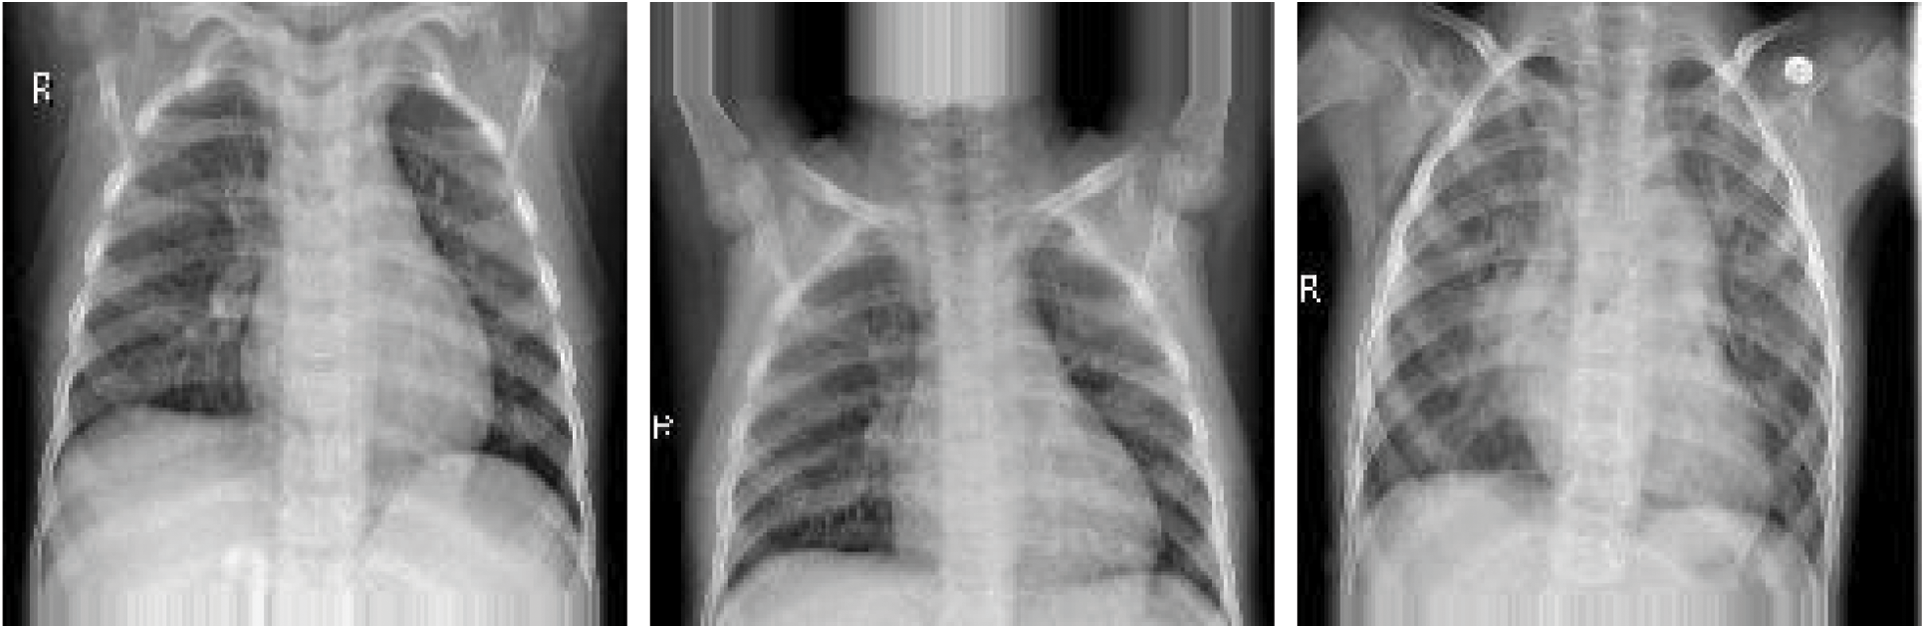

This dataset comprised chest X-ray images of lungs obtained from [29,30]. These images were selected from patients from Guangzhou Medical Center. The dataset is from an open dataset on the Internet. Generally, to obtain hospital images, they must be reviewed and approved by the patient before use. The image is in a standard image format (jpeg) and can be converted to a tensor format for use. The images were categorized into “normal” and “pneumonia” images (Fig. 10).

Figure 10: X-ray image of (a) normal person, (b) pneumonia person

The data set had 1,341 and 3,872 normal and pneumonia images, respectively (at a ratio of 1:3). If the model is trained on imbalanced data, the model is unreliable. This is because the model tends to output guesses for the imbalanced category (with more data points) during training, thus performing poorly on a real-world data set. In addition to this data imbalance problem, the total amount of images was 5,213. The model may tend to learn the category with the higher frequency rather than how to discriminate between categories when making judgments.

Before the model is trained, the images should all have the same pixel count. Data resizing is used to minimize all images to (160, 160). To enable the neural network model to read the images, the image type was converted into NumPy array instead of flipping real X-ray images. The images of normal and pneumonia patients after resizing and transforming them into a NumPy array are shown in Fig. 16. Furthermore, normalization should be done before model training. Since the gray level of the images is between 0 to 255, the NumPy arrays are divided by 255.

Figure 16: Image resizing